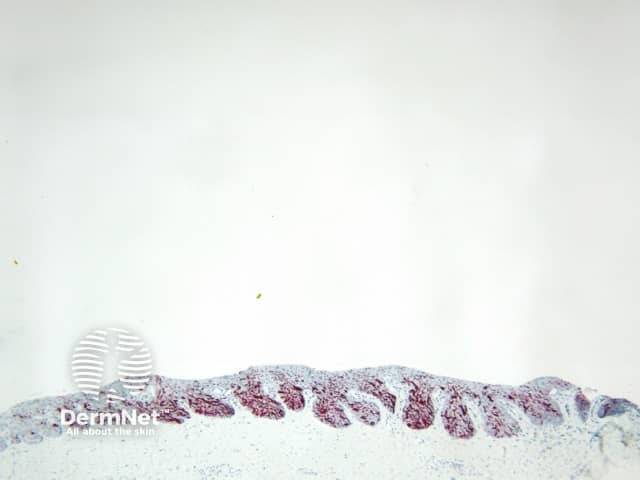

Reticular lines are straight and intersect at regular intervals at right angles. Branched lines are also straight but intersect at irregular intervals and not at right angles. The distinction is not always clear cut and rarely of great importance. These dermatoscopic patterns are seen in lesions in which there is basal epidermal hyperpigmentation and / or a proliferation of pigmented melanocytes preferentially involving the epidermal rete ridges with preservation of the epidermal architecture (Figure 5).

Figure 5